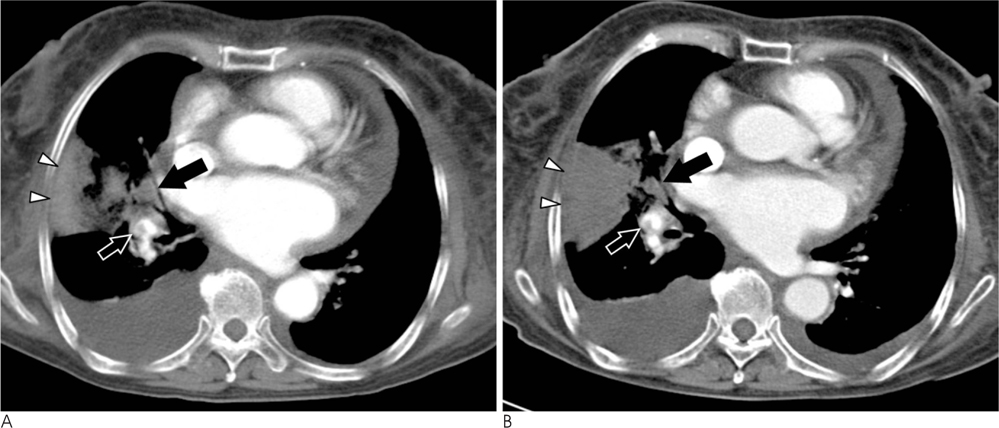

To determine the CT findings of an acute pulmonary thromboembolism for the prediction of response to anticoagulant therapy.

Forty-eight patients diagnosed with a pulmonary embolism underwent anticoagulant therapy, and underwent pre- and post-treatment CT scans, were selected to be part of the study. Pre-treatment CT scans were retrospectively reviewed for the number and degree of emboli, right ventricular to left ventricular (RV/LV) diameter ratio, pulmonary arterial to aorta (PA/aorta) diameter ratio, ventricular septal bowing, consolidation, mosaic perfusion, and pleural effusion. The response to anticoagulant therapy was assessed by a change in embolic burden on pre-and post-treatment CT scans. The 48 patients were divided into two groups: good responder and poor responder. The pre-treatment CT findings were compared by group to determine if there were any differences in the CT findings.

RESULTS

Thirty patients were categorized as good responders (62.5%) and eighteen patients as poor responders (37.5%). A pleura-based wedge-shaped consolidation was observed in 9 of 18 cases (50%) from the poor responder group and one of 30 (3%) cases from the good responder group. The comparison of the finding by group was found to be significantly different (p<0.001). No other CT findings were significantly different between the good and poor responders.

CONCLUSION

The pre-treatment CT scans of patients with acute pulmonary embolism indicate that pleurabased wedge-shaped consolidations can predict a poor response to anticoagulant therapy.